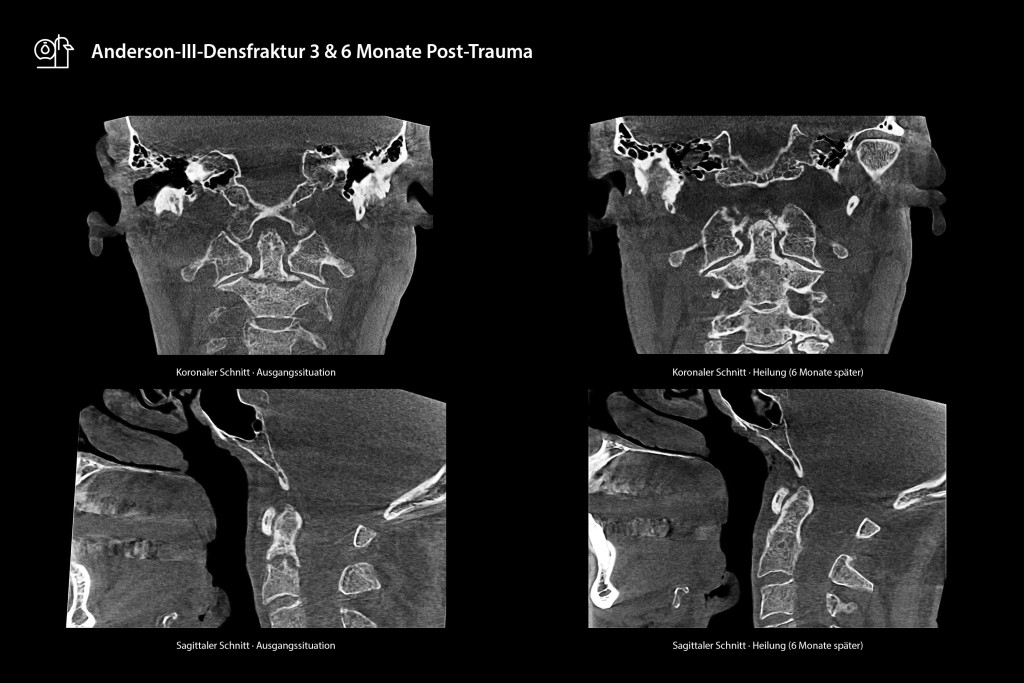

Die erste Kontrolluntersuchung nach drei Monaten mittels SCS MedSeries® H22 DVT, das über ein Super-Ultra-Low-Dose (SULD) Dosisprofil verfügt, dokumentierte eine ungleichmäßige, initial nur zaghaft einsetzende Kallusbildung bei eingeschränkter HWS.

Die hochauflösende 3D-Rekonstruktion des DVT ermöglichte die präzise Darstellung der Frakturspaltmorphologie und frühzeitige Detektion einer drohenden Pseudarthrose, ohne dass eine sofortige operative Intervention erforderlich wurde. Nach ausführlicher Aufklärung über operative Revisionsmöglichkeiten entschied sich der Patient explizit für die Fortsetzung des konservativen Vorgehens unter verlängerter Sportpause und milder Physiotherapie. Die Sechsmonatskontrolle mit dem DVT demonstrierte eine vollständige Frakturdurchbauung mit stabiler Kortikalis und nahezu lückenloser Knochenkontinuität ohne Restinstabilität. Schmerzfreiheit und vollständige Belastbarkeit bestätigten den konservativen Therapieerfolg.